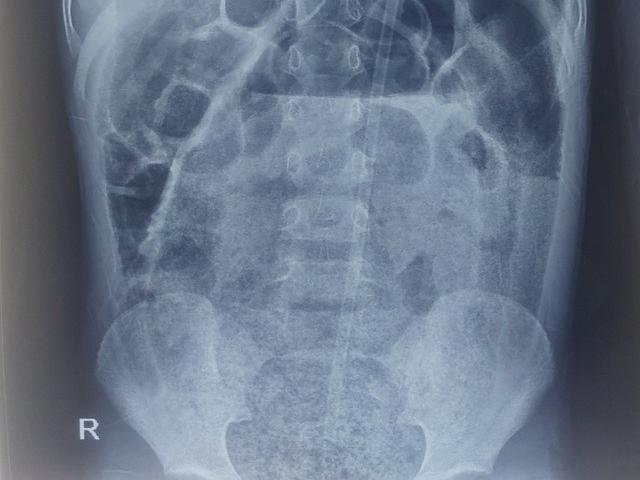

Tại khoa Phẫu thuật nhi, các bác sĩ thăm khám thấy trẻ bụng trướng căng, quai ruột nổi, bệnh nhi nôn dịch nâu bẩn, không đại tiện. Bóng trực tràng rộng, phía trên có khối phân to làm gấp đại tràng, dùng sonde không đẩy lên được để thụt tháo. Chụp X-quang quai ruột giãn to, chứa nhiều phân.

Trong mổ, các bác sĩ thấy quai đại tràng giãn to, đè gập góc gây tắc ruột.